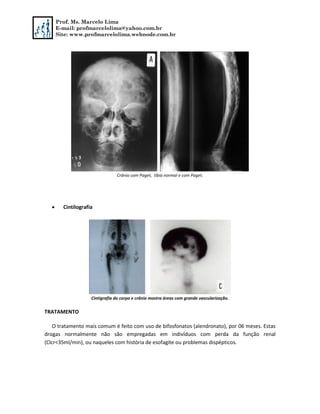

Crânio com Paget, tíbia normal e com Paget.

 Cintilografia

Cintigrafia do corpo e crânio mostra áreas com grande vascularização.

TRATAMENTO

O tratamento mais comum é feito com uso de bifosfonatos (alendronato), por 06 meses. Estas

drogas normalmente não são empregadas em indivíduos com perda da função renal

(Clcr<35ml/min), ou naqueles com história de esofagite ou problemas dispépticos.